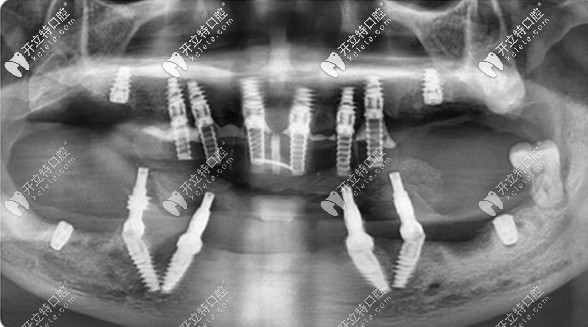

【终期方案为——all-on-4/6全口即拔即种 即刻负重的种植方案】

在充分了解了邓老师的口腔情况和诉求后,擅长全口缺牙修复的王锋医生为她定制了全口即拔即种的方案。

全口拔牙+即刻种牙+当天用牙,对家在泸州的邓老师来说,不仅避免了来回奔波,还避免了缺牙期对自己形象、工作和日常生活的影响。